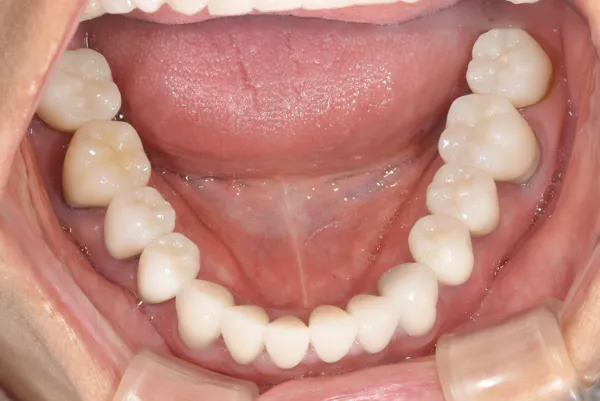

審美歯科治療例8

金属でつめてあったものを、オールセラミックにやりかえたケースです。

従来は金属の詰め物ですが、点線で囲んだ部分はオールセラミックです。

主訴 金属の詰め物を白くしたい

治療方法 金属の詰め物を除去し、セラミックで治療を行った

治療期間 約1ヶ月

通院回数等 4回

費用 66,000円(税込)

リスク・副作用 色調を合わせるのが難しい